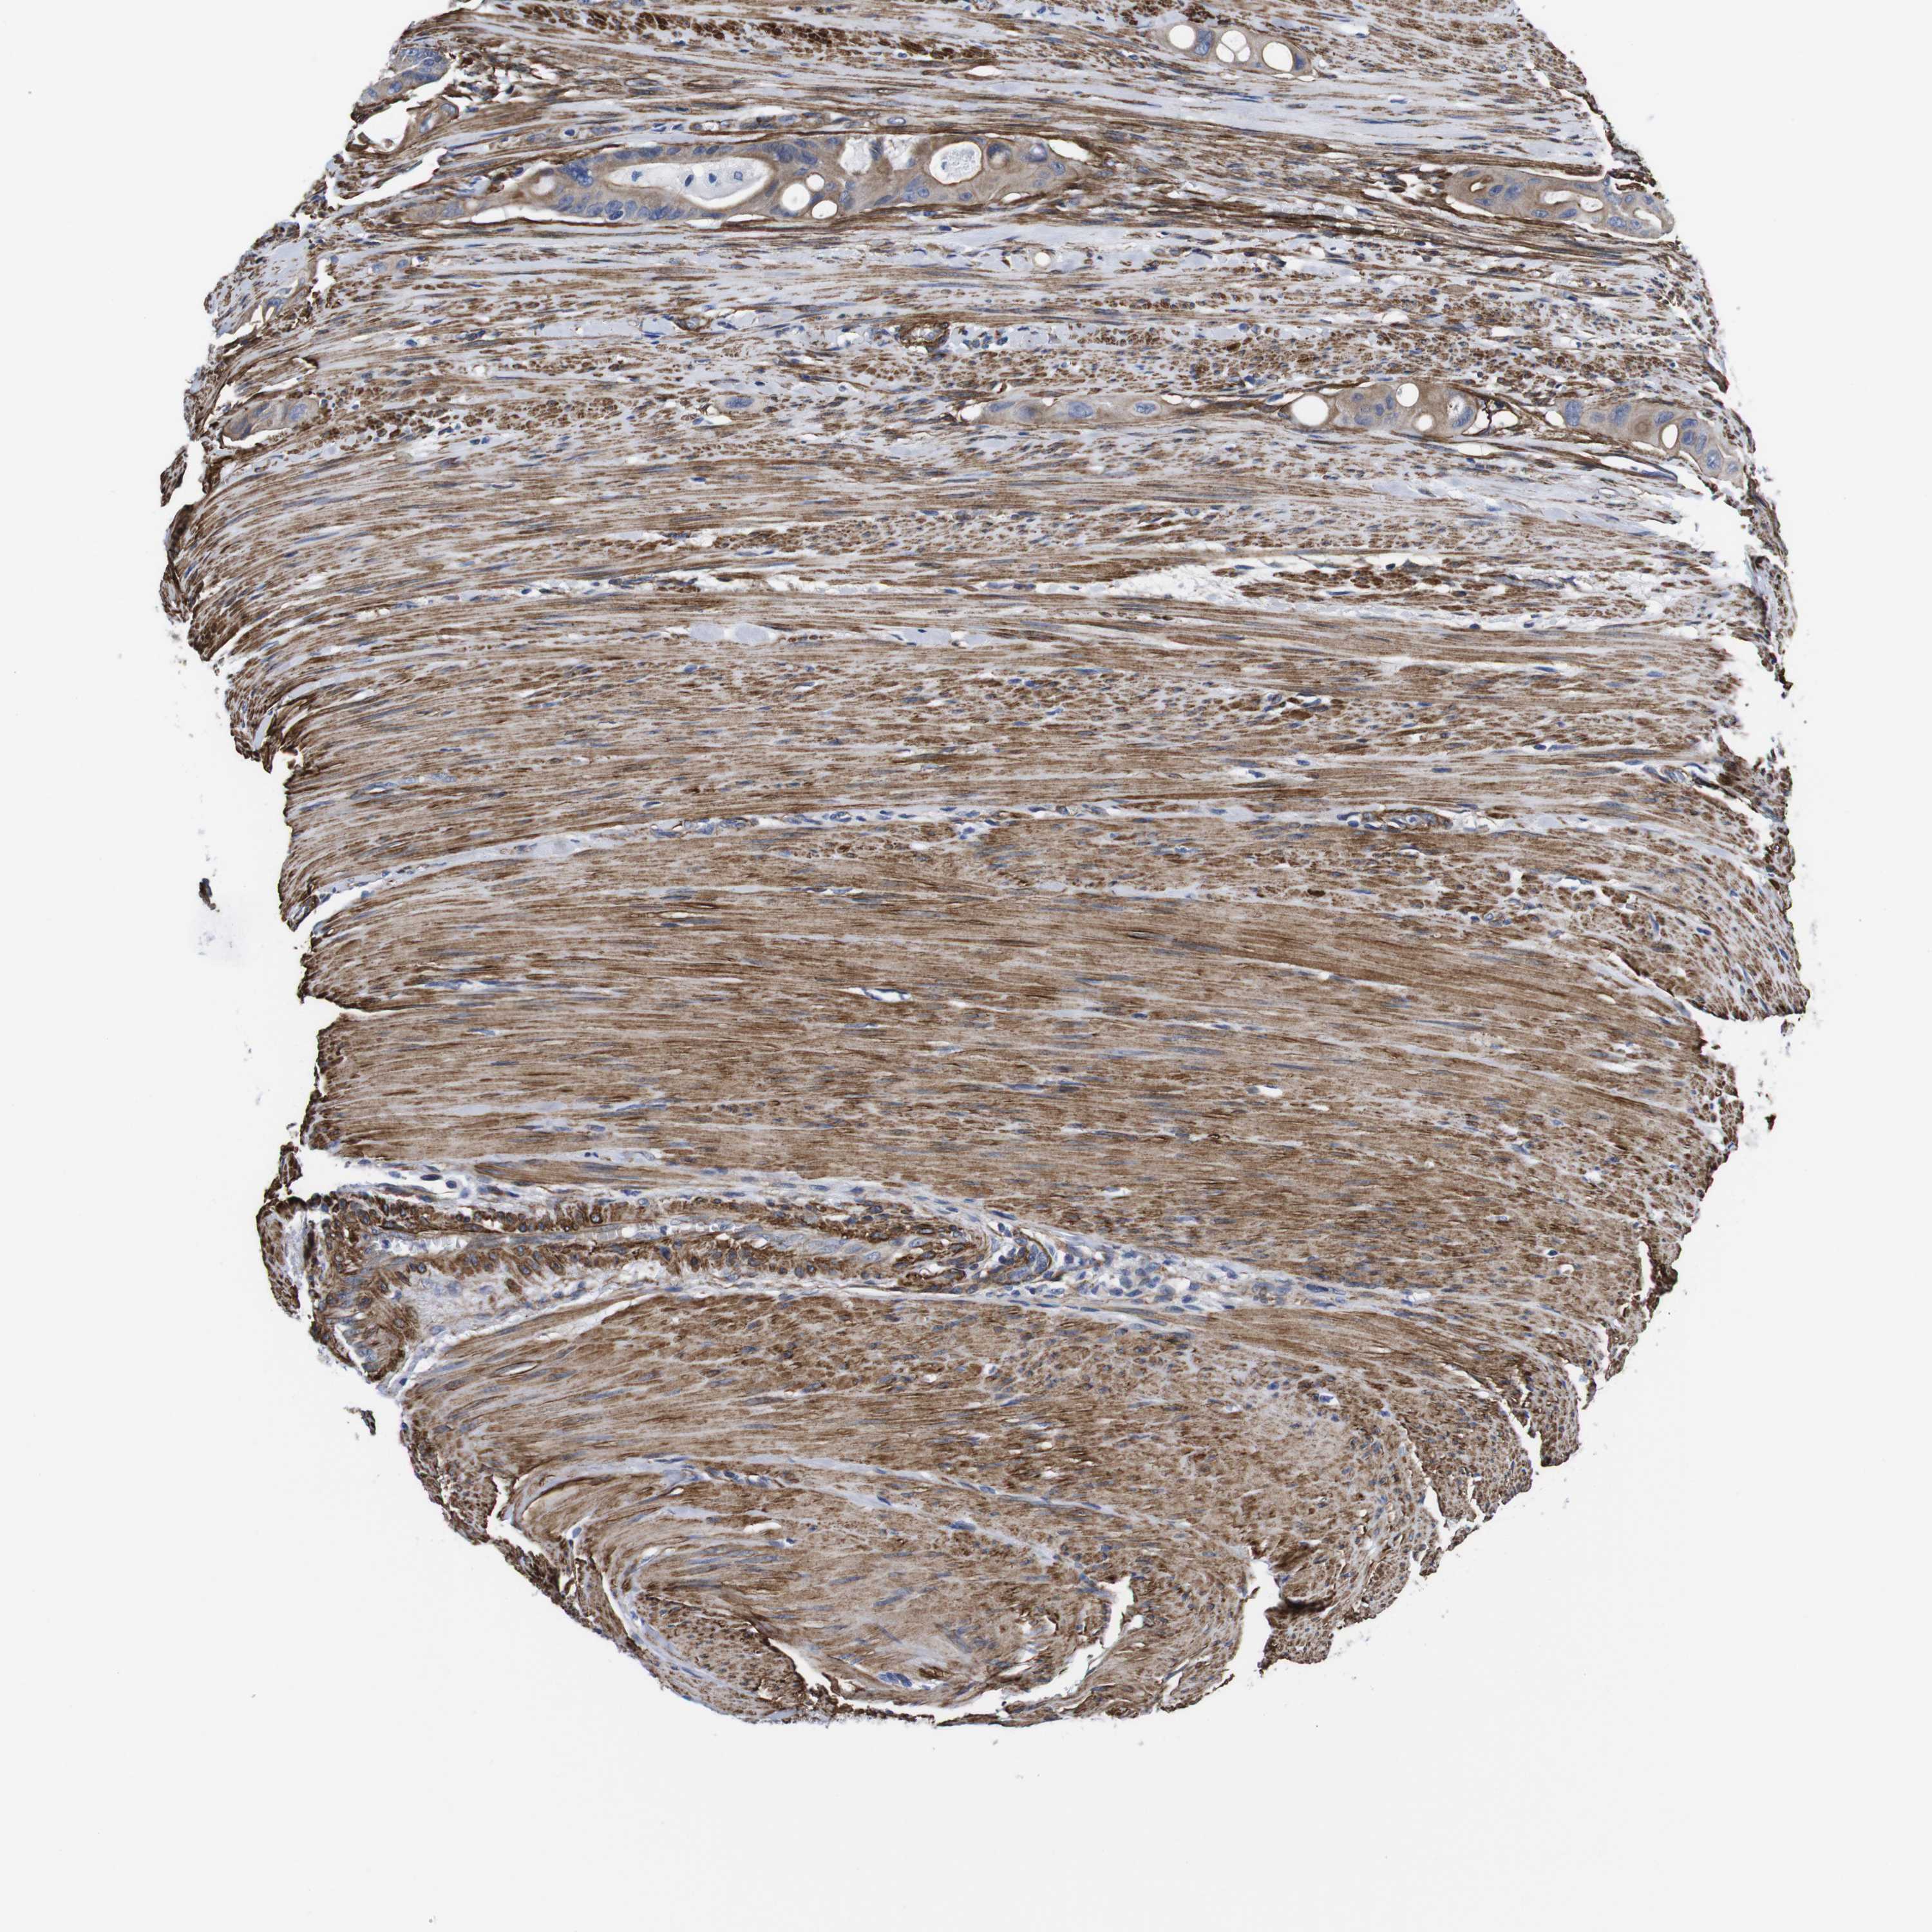

CANCER COLORECTAL CANCER Show tissue menu

Colorectal cancer

Colon adenocarcinoma